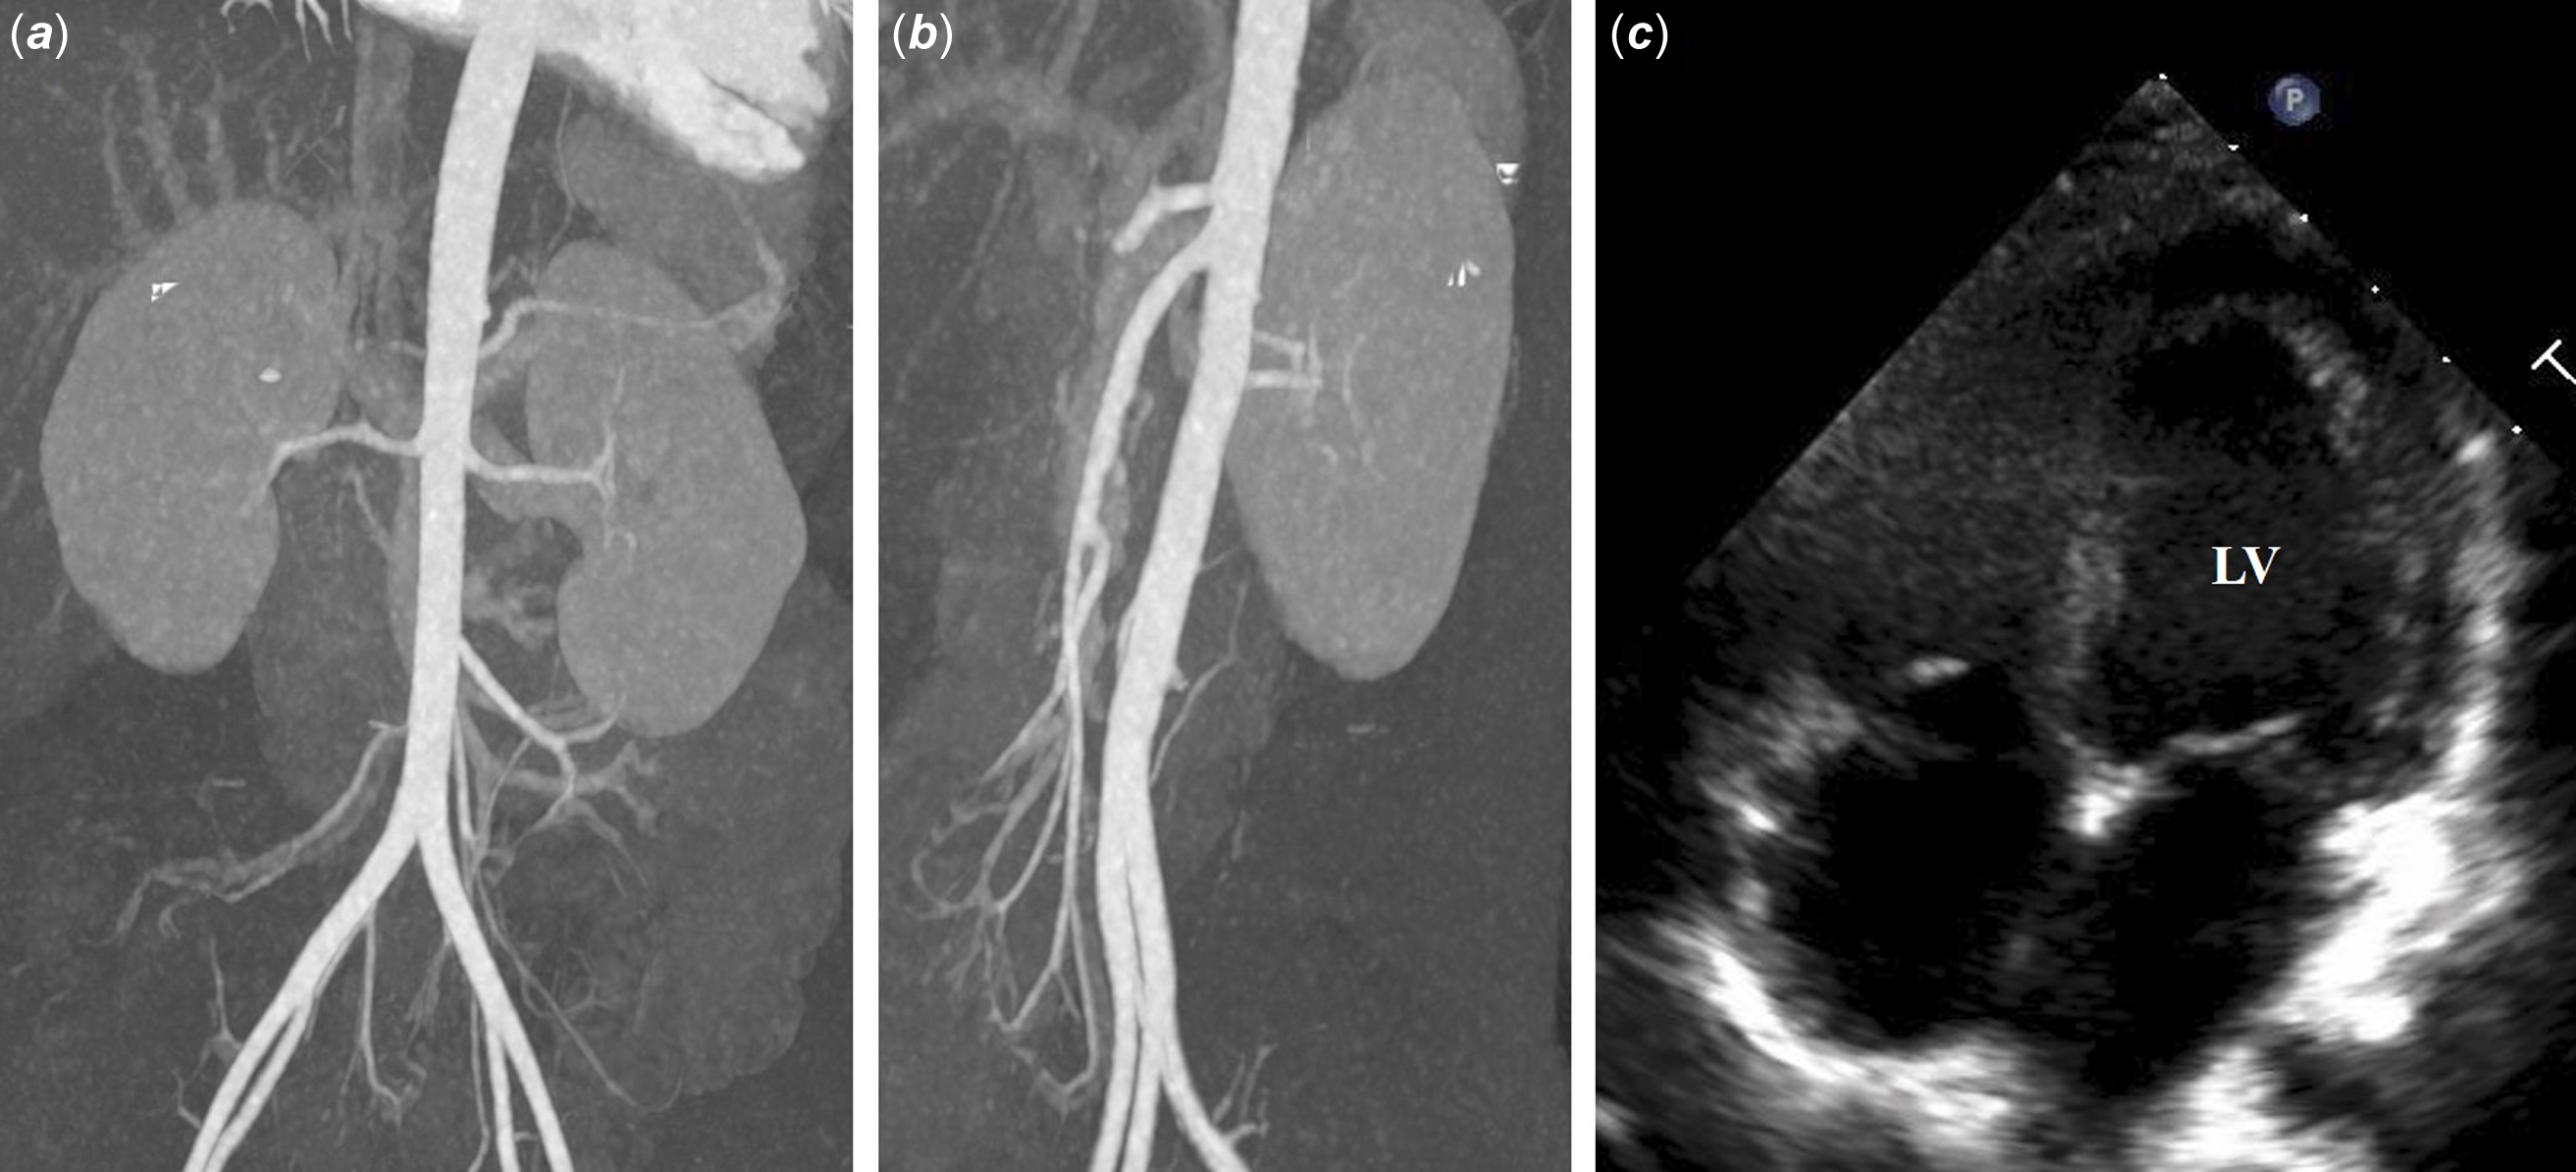

A child with spontaneous resolution of idiopathic mid-aortic syndrome presented with dilated cardiomyopathy

Mid-aortic syndrome is an uncommon vascular disease characterised by lower thoracic and upper abdominal aorta stenosis and can occur even in neonatal or infant periods. Here, we report an interesting case of a 2-month-old female with diffuse hypoplasia of the lower abdominal aorta and secondary dilated cardiomyopathy. In our patient, her abdominal aortic narrowing spontaneously normalised over time with the administration of consistent and goal-directed heart failure therapy, supporting adequate growth and natural recovery.